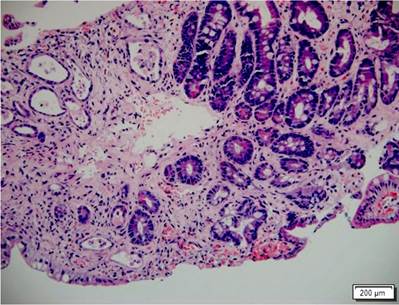

Por medio de una colonoscopia se accedió al íleon y se encontró atrofia difusa de la mucosa, ausencia de vellosidades, además de marcada friabilidad con sangrado fácil y esfacelación al roce, sangrado moderado e inclusive formación de pequeños hematomas submucosos a la toma de biopsias (Figura 2). La mucosa colónica se encontraba normal. El estudio histopatológico de las biopsias tanto de duodeno como de íleon permitió confirmar el diagnóstico de EICH agudo grado 4/4 (Figura 3). La evolución del paciente fue tórpida con persistencia de la diarrea, alto gasto fecal, sangrado digestivo, desórdenes hidroelectrolíticos de difícil manejo, múltiples transfusiones de hemocomponentes, desarrollo de bacteriemia por Klebsiella pneumoniae y falla respiratoria hipoxémica. Se consideró que cursó con EICH aguda, grave y refractaria a esteroides, con criterios de mal pronóstico, y cuyo desenlace fue la muerte 56 días después de la hospitalización.